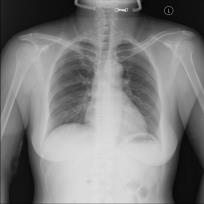

Chest X-ray (CXR) is the most typical radiological exam for diagnosis of various diseases. Due to the expensive and time-consuming annotations, detecting anomalies in CXRs in an unsupervised fashion is very promising. However, almost all of the existing methods consider anomaly detection as a One-Class Classification (OCC) problem. They model the distribution of only known normal images during training and identify the samples not conforming to normal profile as anomalies in the testing phase. A large number of unlabeled images containing anomalies are thus ignored in the training phase, although they are easy to obtain in clinical practice. In this paper, we propose a novel strategy, Dual-distribution Discrepancy for Anomaly Detection (DDAD), utilizing both known normal images and unlabeled images. The proposed method consists of two modules, denoted as A and B. During training, module A takes both known normal and unlabeled images as inputs, capturing anomalous features from unlabeled images in some way, while module B models the distribution of only known normal images. Subsequently, the inter-discrepancy between modules A and B, and intra-discrepancy inside module B are designed as anomaly scores to indicate anomalies. Experiments on three CXR datasets demonstrate that the proposed DDAD achieves consistent, significant gains and outperforms state-of-the-art methods. Code is available at https://github.com/caiyu6666/DDAD.